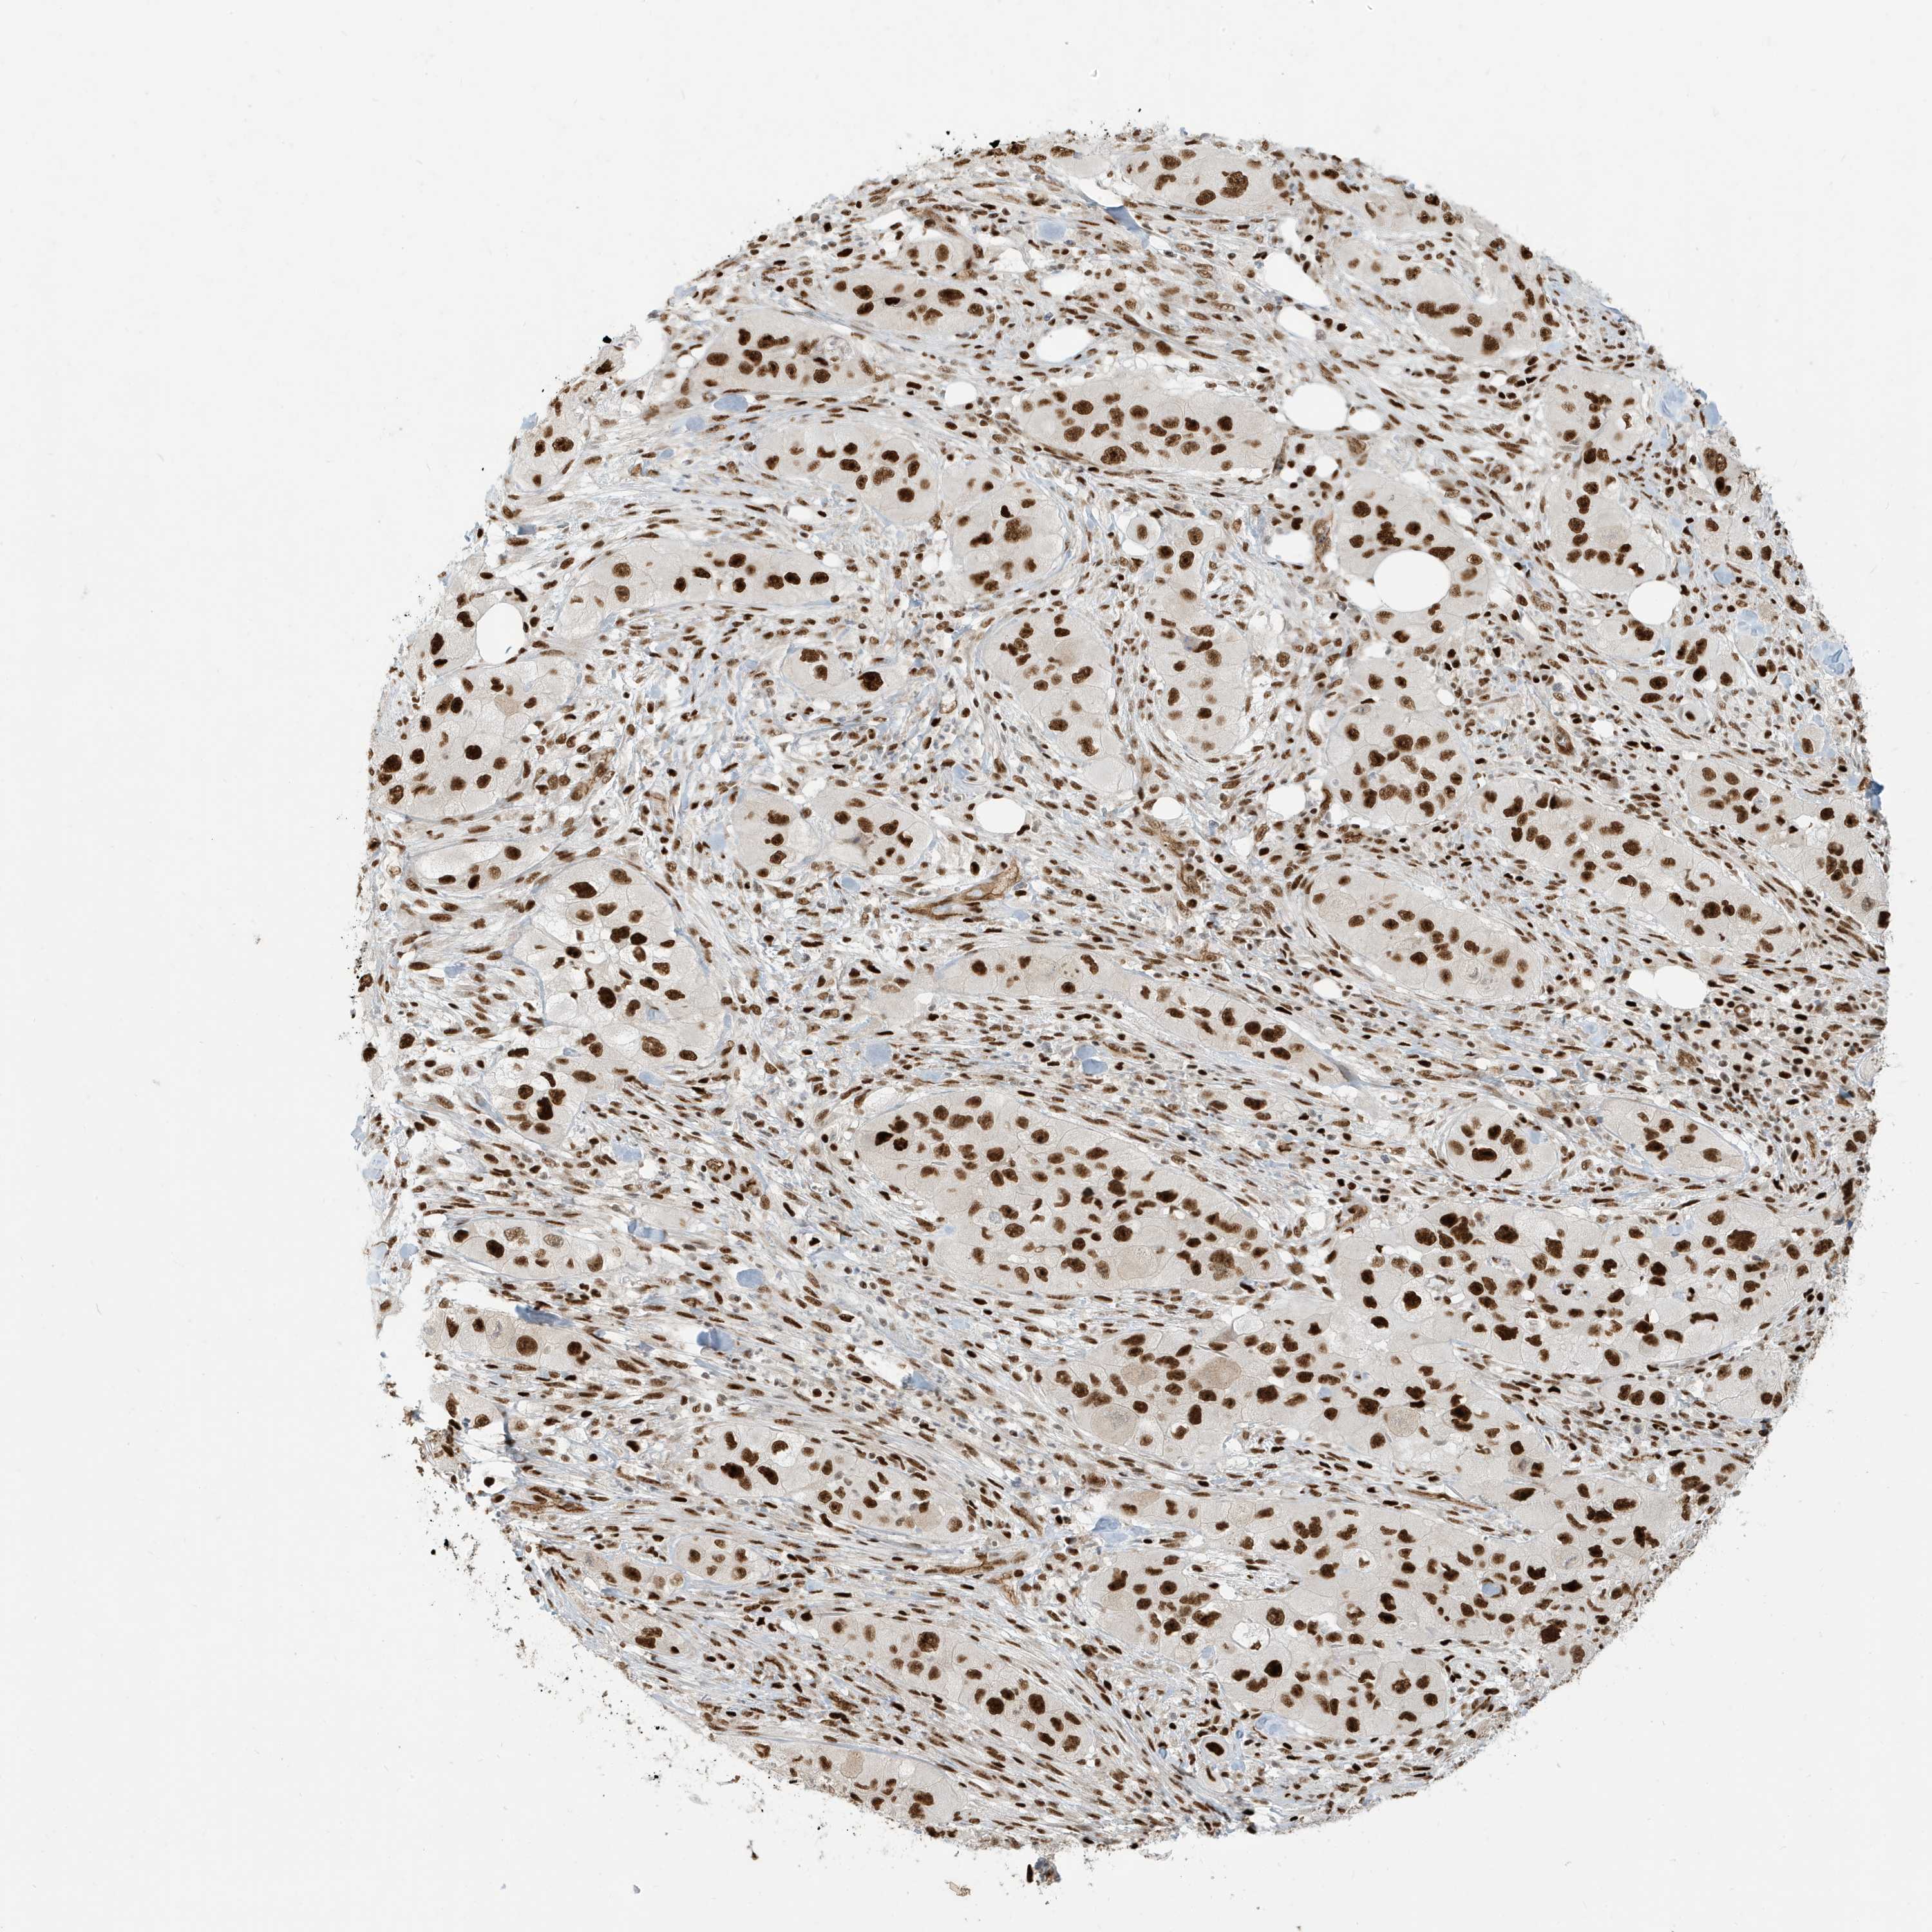

Basal cell and squamous cell cancer

SKIN CANCER - Protein expressioni

A mouse-over function shows sample information and annotation data. Click on an image to view it in a full screen mode. Samples can be filtered based on level of antibody staining by selecting one or several of the following categories: high, medium, low and not detected. The assay and annotation is described here.

Each image is clickable and will lead to virtual microscopy that enables deeper exploration of all samples and also displays staining intensity scores, fraction scores and subcellular localization as well as patient and tissue information for each sample.

Antibody HPA030762

Staining

Medium

Intensity

Moderate

Quantity

75%-25%

Location

Nuclear

Squamous cell carcinoma, NOS